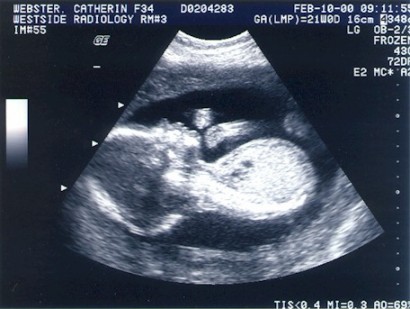

And here I am at 21 weeks